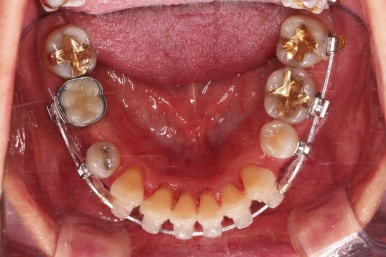

아랫니가 윗니보다 더 많이 삐뚤어 있는데요.

비밀은 바로 화살표에 있습니다.

유치 잔존

말그대로 어릴 때 빠져야 할 유치가 남아있다는 뜻인데요.

앞니 사이에 뾰족하게 남아있다 보니 자리만 많이 차지하고 있는 모습이었고 다른 영구치를 더 삐뚤게 만들었어요.

딱히 영구치가 모자라진 않는데 유치가 잔존하는 굉장히 드물고 독특한 상황이었습니다.

당연히 유치는 뽑기로 했고요.

아직 아래 앞니에 있는 유치는 발치하지 않았는데요.

현 상태로 발치를 하게 되면 기구 접근이 되지 않아 광범위하게 뼈를 갈아내며 뽑아야 됩니다.

교정을 하면 기구 접근이 충분히 되도록 공간을 벌린 뒤 발치를 할 수 있어 기간은 더 걸릴 수 있겠지만 잇몸뼈를 보존하고 수월하게 발치를 하려면 교정만한게 또 없죠.

적절한 시점에 유치를 뽑아내고 남은 공간을 줄여나갑니다.